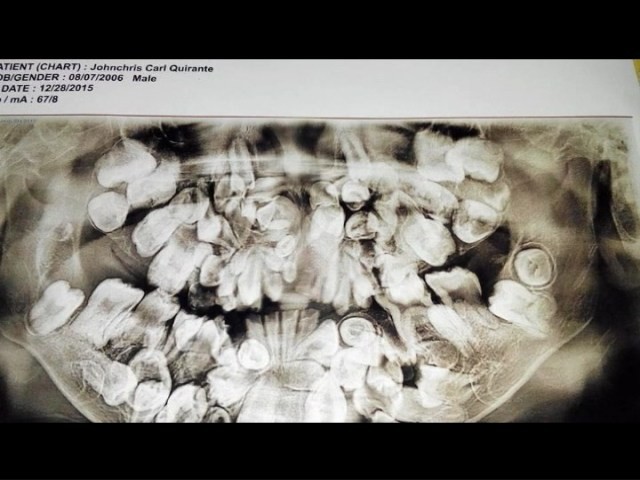

Dù vậy, Johncris vẫn tới trường và hoàn thành xuất sắc việc học. Hiện tại, cậu bé đang học lớp 4. Giáo viên cho biết, Johncris là một trong những học sinh giỏi nhất trường, dù ban đầu gặp khó khăn trong vấn đề giao tiếp nhưng cậu bé đã vượt qua và hòa nhập với bạn bè đồng trang lứa. Johncris hi vọng một ngày nào đó sẽ trở thành kỹ sư.

Tình trạng mọc thừa răng ở trẻ em ảnh hưởng tới 1-4% dân số thế giới và khả năng xảy ra ở nam giới cao gấp đôi so với nữ giới. Các nhà nghiên cứu không chắc chắn nguyên nhân thực sự gây ra tình trạng này, nhưng họ tin rằng một phần có thể do yếu tố di truyền và môi trường sống.